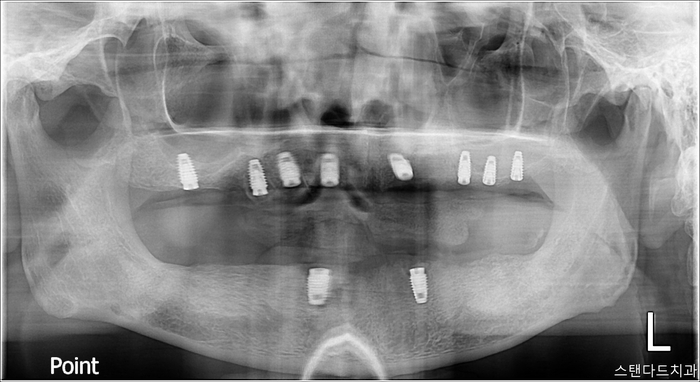

수술 직 후

촬영:2023년 10월 10일

하악은 계획대로 2개를 식립했고

상악은 왼쪽의 뼈가 약해서 추가로 1개 더 식립해 드렸습니다.

물론 비용은 추가되지 않습니다

(수면치료 중 추가로 의료진의 판단으로 필요하다고

생각되는 곳에 추가로 식립하는 부분에 대해서는

따로 비용을 받지 않고 있습니다. 이게

환자와 의사를 위해 이롭다고 판단하기 때문입니다)

임플란트 완성(최종보철 체결)

촬영:2024년 3월 25일

총 5개월에 걸친 치료 끝에

상악은 전체임플란트 하악은 임플란트 틀니로

최종 보철 체결해 드렸습니다.